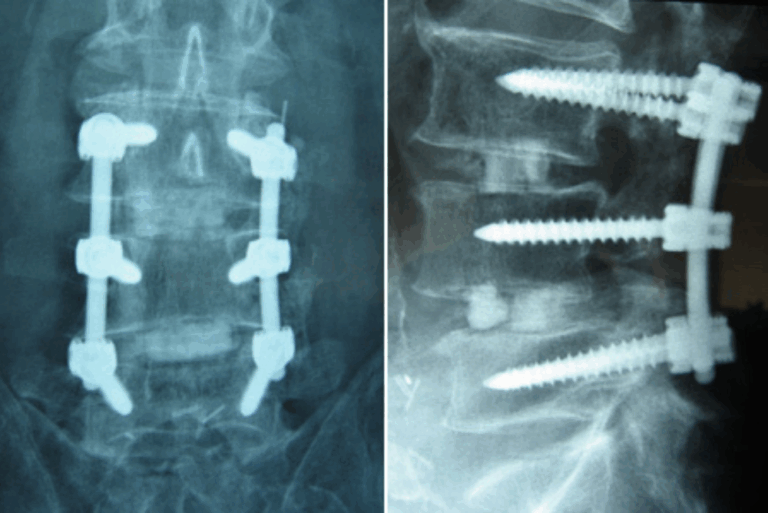

Modern Implants and Materials

Fusion hardware has evolved as well. Today’s implants are designed to:- Match patient anatomy more closely

- Support proper spinal alignment

- Encourage better bone healing

- Reduce implant-related complications

Navigation and Imaging Improvements

Technology now helps surgeons see more — and plan better. Advanced imaging and navigation systems allow for:- More precise screw placement

- Better spinal alignment

- Reduced reliance on guesswork

- Improved consistency from case to case